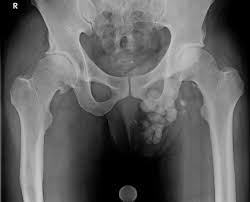

Scrotal calcinosis is a rare and benign clinical disorder of the skin which involves the accumulation and deposition of calcium and phosphorus crystals in the cutaneous tissues of the skin of the scrotal area in men.

Meanwhile, the blood level of these two components; calcium and phosphorus remain normal in the patients of scrotal calcinosis. It is most prevalent in men of younger age during their age of adolescence. Mostly this disease shows no clinical manifestation but in some patients it can be very painful involving the occurrence of hard yellow bumps on the skin of scrotum which may range in size from 1mm to few centimeters. These nodules or bumps are calcium or phosphorus deposits mainly located in the dermis of the scrotum and surrounded by a type of foreign granulomatous material.

There are mainly five types of calcinosis and one of them is idiopathic (meaning no known cause of occurrence of the disorder) which involves the occurrence of calcified nodules only on one specified area of the body and without the increased blood levels of calcium. So scrotal calcinosis meets with these criteria and so is also called idiopathic scrotal calcinosis.